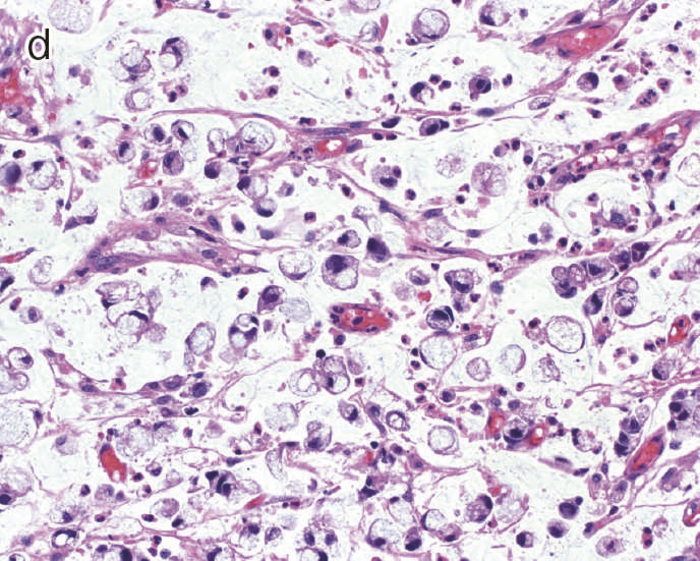

dysplasiaはその異型度によりLGDとHGDに二分される(図9)。LGDは基本的に核の極性が比較的保たれており,表層への分化傾向がみられることを特徴とし,しばしば反応性異型との鑑別を要する。多彩な形態像を示すこともdysplasiaの特徴である。味岡らは,UC関連大腸腫瘍を5つの特殊なパターン(表層分化を示す分化型腺癌,分化細胞を豊富にもつ分化型腺癌,分化細胞に乏しい分化型腺癌,未分化型腺癌または分化型腺癌の脱分化,癌の判定が困難な分化型腫瘍)に分類し報告している3)。2019年に出版されたWHO分類には,IBDを背景に発生する粘膜内腫瘍をInflammatory bowel disease-associated dysplasia of the colorectumと呼称し,組織形態に基づき,intestinal(adenomatous)subtype,serrated subtype,mucinous type,a subtype with eosinophilic cytoplasm and marked goblet cell depletion,crypt cell subtypeやこれらの組織像が混在したmixed subtypeなどが存在すると記載されている4)(図10)。

- UC関連粘膜内低分化腺癌:粘膜内において粘液癌あるいは印環細胞癌が認められる。

- cの拡大像。